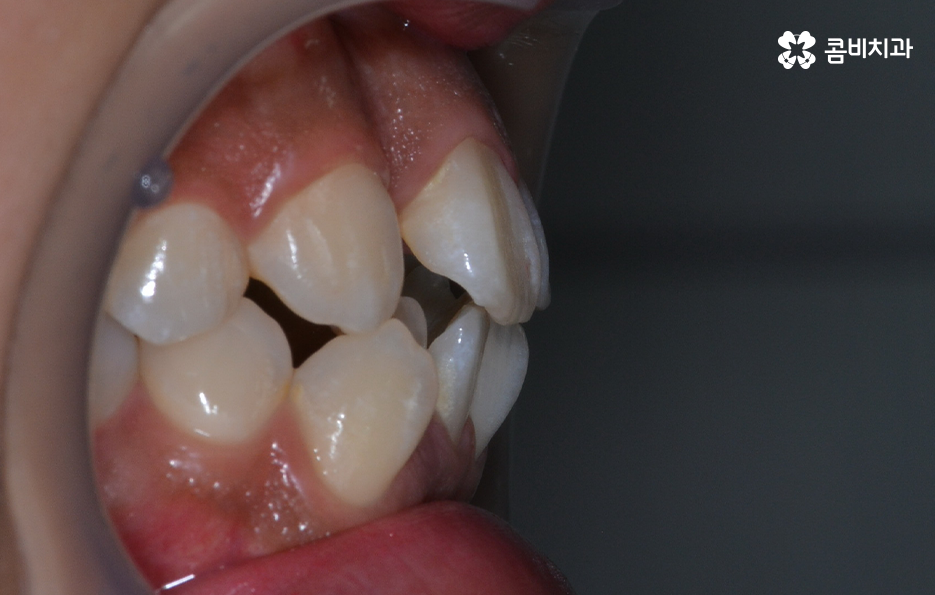

심한 덧니라도 비발치 교정은 어려운 건가요

덧니의 주된 원인이 턱뼈가 좁아서 치아가 자랄 공간이 부족하다 보니 덧니의 형태로 영구치가 자라는 경우가 많다 보니 전체 치열을 가지런하게 재배열 하기 위해서는 충분한 치아의 이동 공간이 필요하고 치아의 이동 공간을 확보하는 방법으로 주로 소구치 즉 작은 어금니를 발치하는 발치교정 방식이 보편적으로 많이 활용되고 있는데요

앞니의 덧니가 심하고 겹쳐 있는 경우에는 교합이 제대로 맞물리지 않거나 이물질이 치아 사이에 끼기 쉽고 그로 인해 치석이 쌓이기 때문에 나이가 들수록 덧니를 방치할 경우 충치 뿐 아니라 치주질환의 가능성이 높아지고 있는데요

덧니 교정을 통해서 치아 교합의 기능적 개선과 치아 관리의 용이성 높일 수 있고 치아 건강에도 도움이 되며 심미적인 개선도 도움이 될 수 있어요